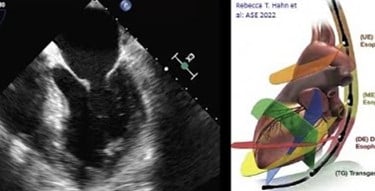

O ETE é um exame de ultrassom avançado que oferece imagens detalhadas do coração e grandes vasos através de um transdutor especial introduzido pelo esôfago. Esta localização privilegiada permite visualizar estruturas cardíacas com extraordinária clareza, superando limitações do ecocardiograma tradicional.